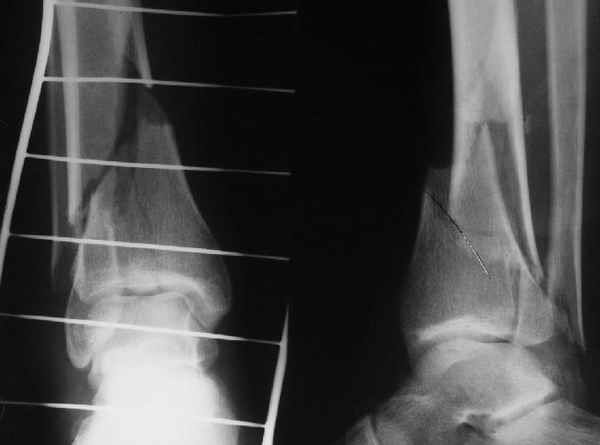

АЧ>Какие тут аргументы в пользу выбора пластины, а не интрамедуллярного гвоздя?

Классически показанием для locked nail яв-ся зоны BC CD, до появления LCP показания к locked nail несколько расширялись в зоны AB и DE

Аргументы: перелом достаточно низкий, трудно будет ввести 3-и блок. винта, а учитывая характер перелома на 2-х дистальных винтах я бы не рекомендовал немедленную полную нагрузку.

С Уважением А.Миронов

Кликните для загрузки файла DSC00841.JPG

42KB (43152 bytes)